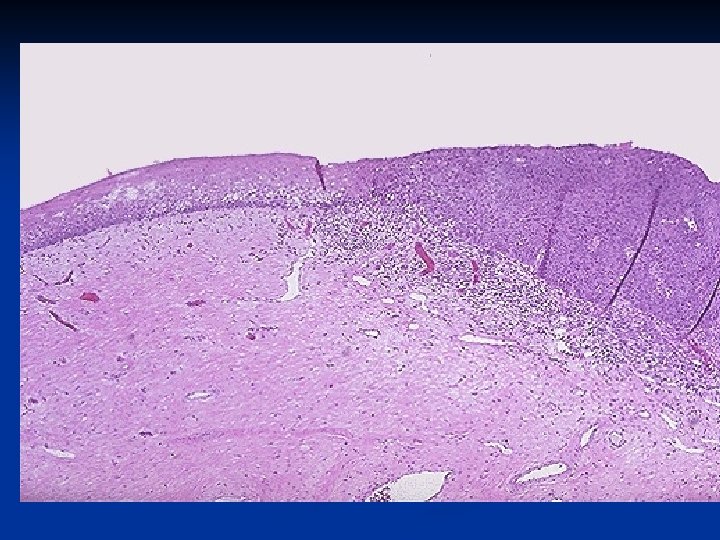

Cervical intraepithelial neoplasia (CIN) n n can exist for years or decades before invasive squamous cancer happens. : -Low grade intraepithelial neoplasia (CIN-I) -High grade intraepithelial neoplasia (CIN-II-CINIII) CIN exploration with PAP smear technique: n Low grade intraepithelial neoplasia CIN I –(LGSIL)(Koilocytes* only) n A condyloma acuminatum or a flat wart or simply squamous metaplasia of the endocervix.

Morphology n n On the extreme low end of the spectrum are lesions that are often indistinguishable histologically from condylomata acuminata and may be either raised (acuminatum) or macular (flat condyloma) in appearance Such changes fall within the range of CIN I- Low grade intraepithelial neoplasia -. CIN I often contains abundant papillomavirus nucleic acids. Raised lesions (acuminatum) often contain low-risk HPVs. Flat CIN usually contain high-risk HPVs.

Spectrum of cervical intraepithelial neoplasia: normal squamous epithelium for comparison Downloaded from: Robbins & Cotran Pathologic Basis of Disease (on 24 February 2006 08: 56 AM) © 2005 Elsevier

CIN I-LGSIL with koilocytotic atypia Downloaded from: Robbins & Cotran Pathologic Basis of Disease (on 24 February 2006 08: 56 AM) © 2005 Elsevier

CIN II -HGSILwith progressive atypia in all layers of the epithelium Downloaded from: Robbins & Cotran Pathologic Basis of Disease (on 24 February 2006 08: 56 AM) © 2005 Elsevier

CIN III (carcinoma in situ) with diffuse atypia and loss of maturation. Downloaded from: Robbins & Cotran Pathologic Basis of Disease (on 24 February 2006 08: 56 AM) © 2005 Elsevier